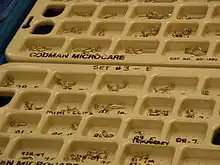

Surgical clipping

Aneurysms can be treated by clipping the base of the aneurysm with a specially-designed clip. Whilst this is typically carried out by craniotomy, a new endoscopic endonasal approach is being trialled.[30] Surgical clipping was introduced by Walter Dandy of the Johns Hopkins Hospital in 1937.[31] After clipping, a catheter angiogram or CTA can be performed to confirm complete clipping.[32]